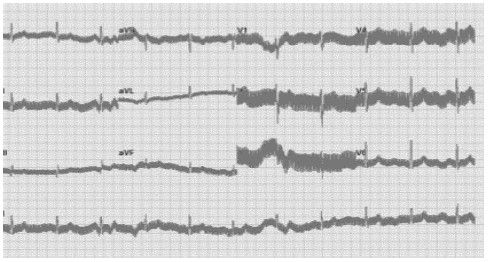

Em um espectro de amplitudes, no domínio da frequência, de uma série de dados coletados por um sistema de eletrocardiografia durante o repouso, foi observado um pico de amplitude em 60 Hz. Qual o motivo mais provável para o aparecimento deste pico de amplitude?